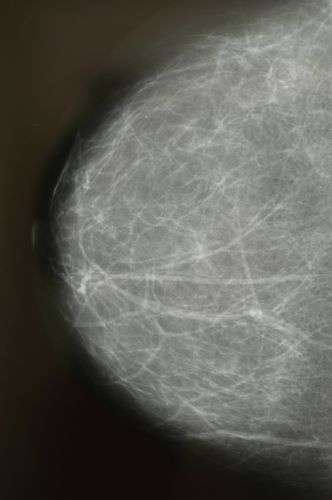

Vorbereitung eines Patienten für eine Operation im Operationssaal

Die Finanzierungsreform soll den Trend zu mehr ambulanten statt stationären Eingriffen verstärken. Bild: Christoph Ruckstuhl / NZZ